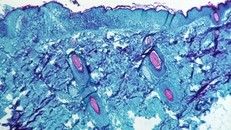

(Ngày Nay) - Bộ Y tế cho biết, bệnh đậu mùa khỉ (monkeypox) không phải là bệnh mới, bệnh được ghi nhận lần đầu tiên vào năm 1958 trên các đàn khỉ được nuôi để nghiên cứu, do đó có tên là bệnh Đậu mùa khỉ.